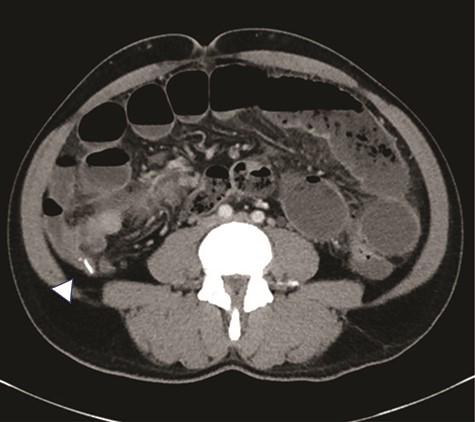

A 47-year-old male presented to the Emergency Department with abdominal pain, nausea, emesis and diarrhea for four days. His last bowel movement was the day prior and he was continuing to pass flatus. On physical examination, his abdomen was soft and nondistended, with tenderness in the epigastrium and left lower quadrant. His vital signs and laboratory values were within normal limits. Computerized topography (CT) scan showed a high-grade SBO with a transition point within distal ileum with asymmetric irregular bowel wall thickening, which was suggestive of a mass (Fig. 1). A moderate amount of ascites was also noted, as well as an appendicolith within the appendix, mildly thickened to 8 mm without any other sign of inflammation (Fig. 2). The patient was admitted to the hospital for initial conservative management, and a cancer work up was initiated for a primary SBO. CT of the chest showed no distant metastases. Tumor markers (carbohydrate antigen 19–9, carcinoembryonic antigen and alpha-fetoprotein) were all within normal limits. Over the next three days, the patient regained bowel function and his pain improved. He opted for outpatient colonoscopy and surgery and was discharged home. Two days later, the patient represented to the ED with abdominal pain, distention and emesis. He had a normal white blood cell count with neutrophilia and lactic acidosis of 3.1. A repeat CT scan of the abdomen and pelvis showed essentially unchanged findings from the prior study. He then was taken to the operating room for exploratory laparotomy. A firm mass was noted 20 cm proximal to the terminal ileum with a mass lesion and an abnormal, firm appendix. We performed a small bowel resection and appendectomy. The patient was subsequently referred to the hematology/oncology department for further treatment. He underwent a bone marrow biopsy which was negative for evidence of leukemia and subsequently began treatment with induction chemotherapy.

There is an appendicolith noted within the proximal appendix which is mildly thickened measuring up to 8 mm (arrowhead).